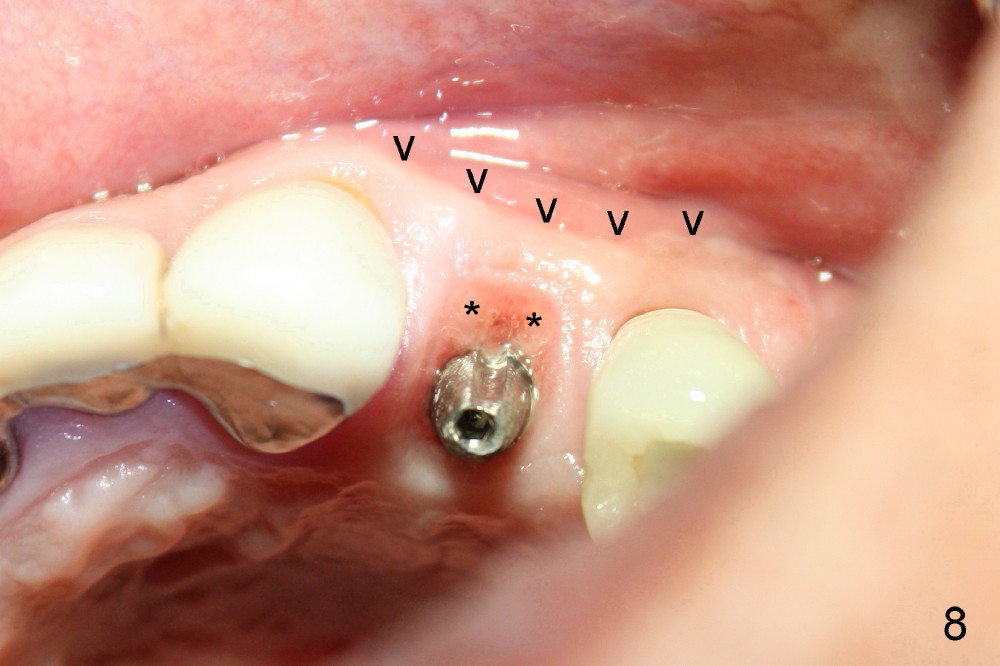

A 50-year-old man has mild pain in the upper left 1st bicuspid 3 years after root canal retreatment with placement of two posts (Fig.1). Findings of clinical exam are consistent with root fracture (Fig.2). Extraction reveals two fused roots (Fig.3,4). Probing indicates that the buccal plate is defective. Osteotomy is initiated in the palatal socket with a 2 mm pilot drill, followed by 2.5 and 3.0 mm reamers and 4.5x20 mm tap. The septum appears to have been pushed buccally (Fig.5 *) and form a new buccal wall (partially, strengthened by bone graft mentioned below) for the implant to be placed. The implant (4.5x20 mm) is placed in the palatal socket (Fig.6 *) with insertion of an abutment (A: 3.5x5 mm 0º), while a mixture of autogenous bone (harvested from reamers) and Synthograft (Bicon) is placed in the shrunken buccal socket (Fig.7; using allograft may decrease postop bony shrinkage). The bone graft is then contained by an immediate provisonal without collagen membrane or flaps. The patient is doing well postop. The gingiva is healthy (Fig.8*) when the provisional is removed 3 months postop with normal papillae (Fig.9 arrowheads). It remains the same 1 month post cementation (Fig.10,11). For further follow up, see immediate implant of the tooth #13.